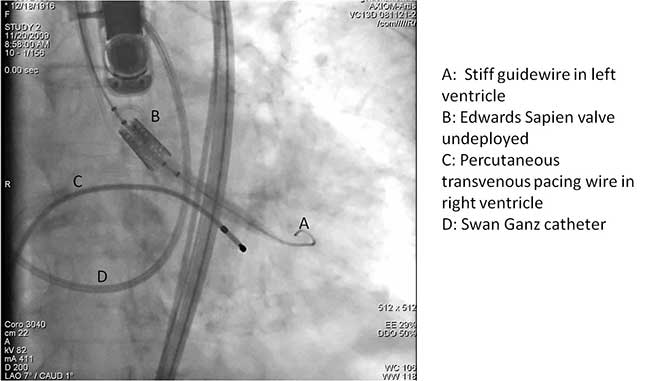

A cut-down is then performed in the ipsilateral groin and the femoral artery is exposed. Using a 18 gauge needle, wire access is achieved in the femoral artery using Seldinger technique. A 14 Fr sheath is then placed in the femoral artery. Using a straight wire through an AL1 guide catheter (Boston Scientific Corporation, Massachusetts), the stenotic aortic valve is crossed and images are obtained to assess the left ventricular outflow tract, the native aortic valve and its relation to the coronary ostia. The AL1 guide catheter is then advanced into the left ventricle and the straight wire is then exchanged for a stiff wire such as an Extra-stiff Amplatz (Cook Medical, Indiana) or Lunderquist guidewire (Cook Medical, Indiana). Next, a balloon aortic valvuloplasty (BAV) is performed with the use of a Tyshak 22 mm balloon (B. Braun Medical Inc., Pennsylvania) to facilitate crossing of the native stenotic valve with the Edwards Sapien valve (Figure 1). BAV is performed during a short period of rapid ventricular pacing to minimize transvalvular flow and potential embolization. It is critical to stabilize hemodynamics after the valvuloplasty due to hypotension from rapid pacing and from the ensuing aortic insufficiency.